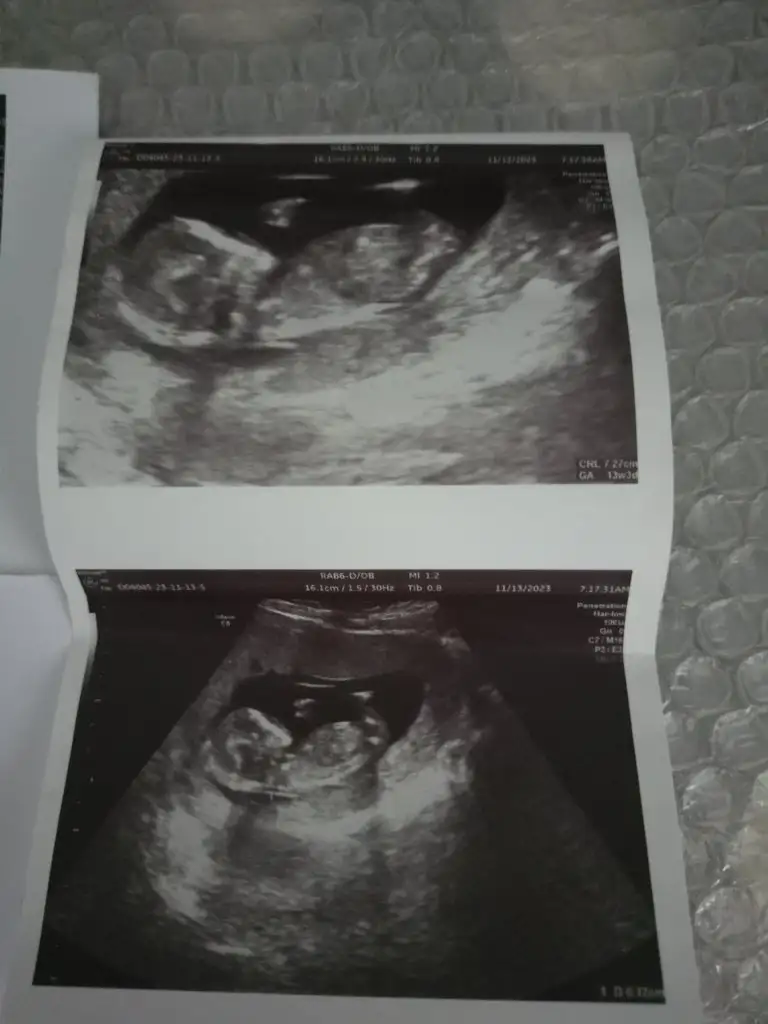

14 haftalik gebeyim doktor soyledi ama yizfe 60 oran verdi kordon gectigi icin keseden anlayan olurmu acaba ❤

• IMG20231113125141.webp

• IMG20231113125327.webp